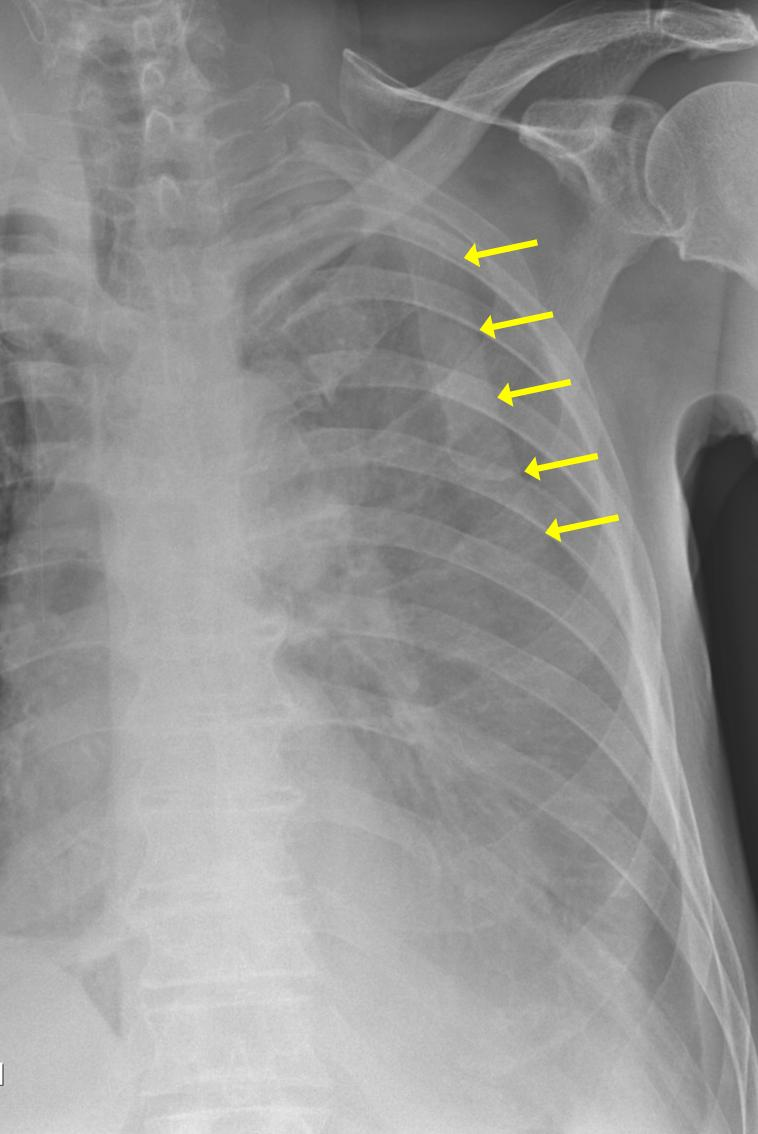

15.2.2.4. In chest trauma

We discuss two conditions

• Pneumothorax or mediastinal free air means that there is free air in either in the pleural cavity or in the mediastinum. This condition is usually apparent on chest x-ray (In injuries there is also blood in the pleural cavity)